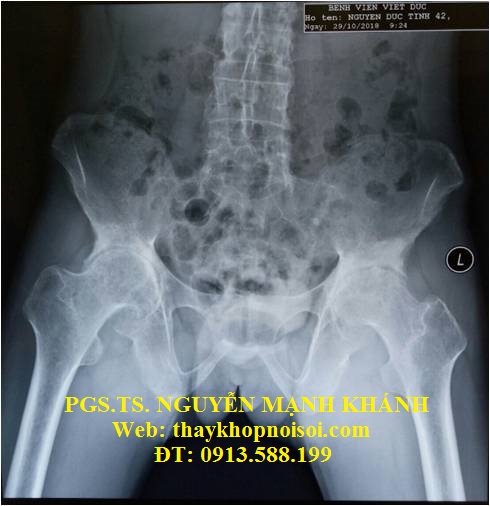

Bệnh nhân nam, 42 tuổi

Địa chỉ: Thạch Thất, Hà Nội

Chẩn đoán: Thoái hóa, viêm dính khớp háng 2 bên

Hình 1. Hình ảnh X-quang thoái hóa, viêm dính khớp háng 2 bên